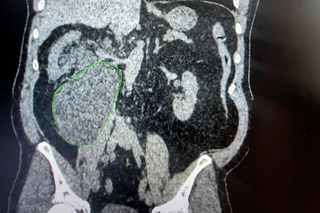

Пациент экстренно обратился в БГКБ. При осмотре и проведении КТ врачи обнаружили в забрюшинном пространстве массивное скопление жидкости — уриному.

Уринома — это скопление мочи вне мочевыводящих путей. Такое осложнение встречается крайне редко (всего в 3-5% случаев) и связано с нарушением герметичности лоханки или чашечки почки.

Ситуация была критической: объём скопившейся мочи составил 1,5 литра. Это огромное образование не только вызывало невыносимую боль, но и сдавливало почку, мешая её нормальной работе», — рассказали врачи.